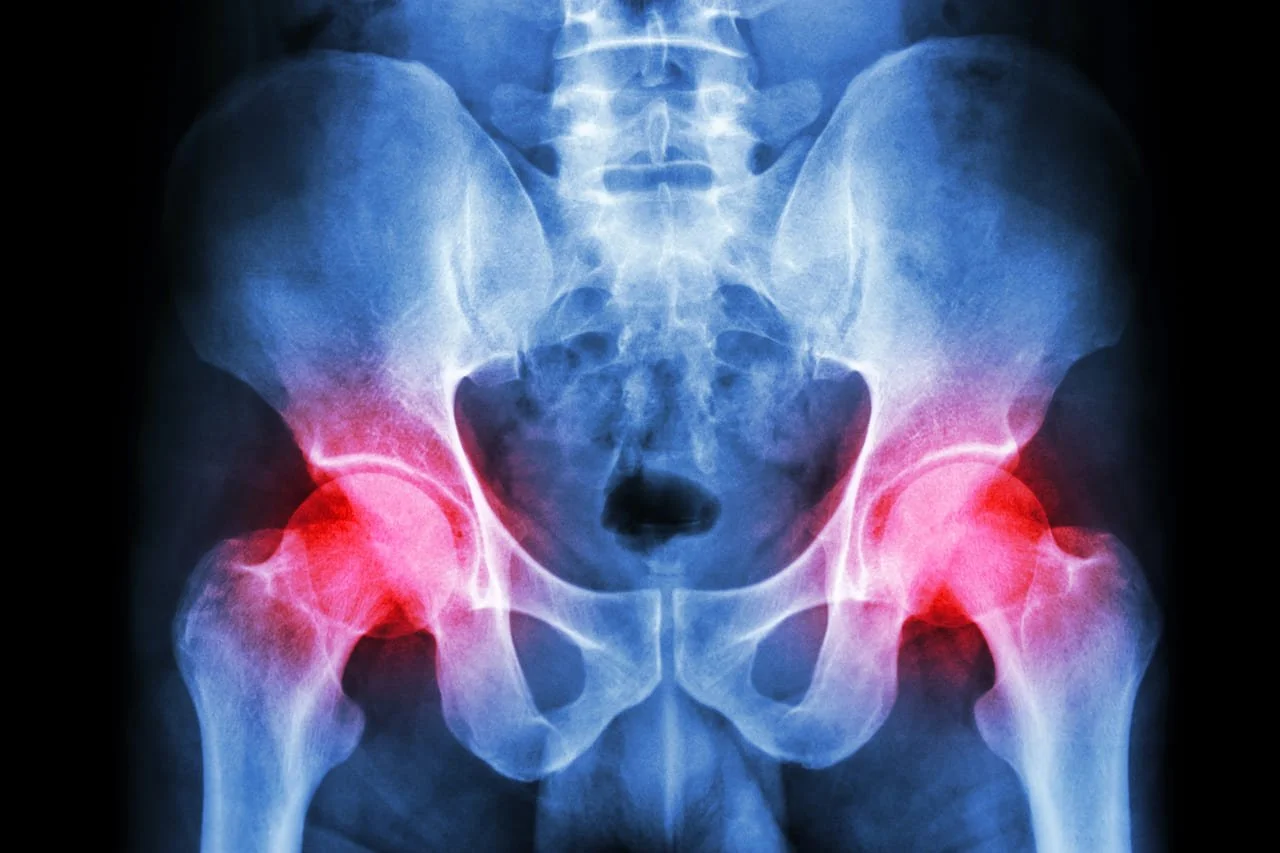

Can Pelvic Physiotherapy Help With Hip, Back, or Core Stability Issues?

The pelvic floor is part of the core muscle group that includes the diaphragm, deep abdominals, and spinal stabilizers. Dysfunction in this area can contribute to broader musculoskeletal issues:

Improved Core Coordination: Therapy enhances how pelvic floor muscles work with the rest of the core to stabilize the spine and pelvis.

Postural Correction: Better alignment reduces strain on the hips and lower back.

Releasing Muscle Imbalances: Tight or underused muscles in the pelvic region can lead to compensation and pain elsewhere.

Functional Movement Training: Therapists retrain movement patterns to reduce injury risk and enhance performance.

Pain Reduction Strategies: Addressing pelvic dysfunction may resolve referred pain in the back or hips.

Targeted Strengthening: Customized plans support core resilience in day-to-day activities and exercise.

Pelvic physiotherapy is a key player in addressing pain and improving function beyond the pelvic region.